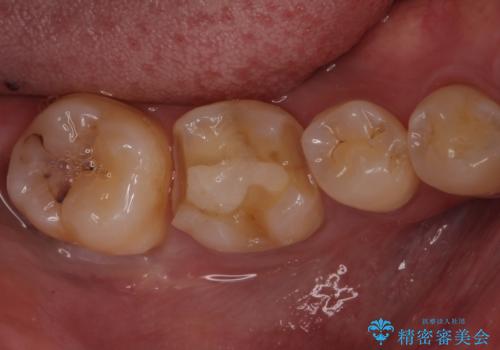

古いセラミックを外すと、無数のヒビが入っており、そこからできた新しい虫歯がありました。

古い材料も虫歯もすべて除去して、根本からやりかえました。

セラミックが欠けるほど強い力がかかっているということは、ご自身の歯も割れている(小さいヒビ等も含む)可能性があります。拡大鏡でしっかり見ながら治療します。